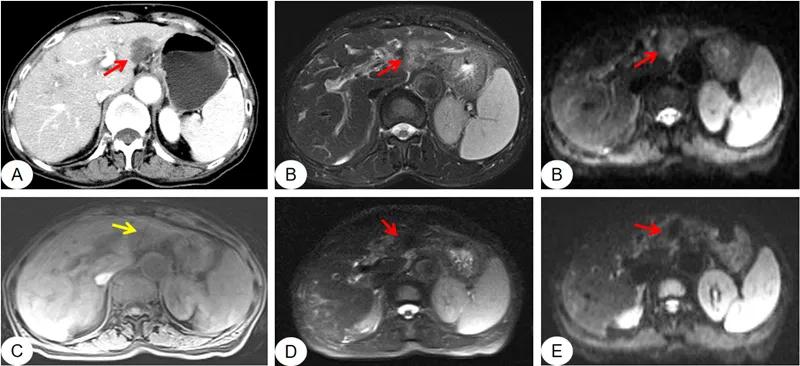

图示:CT增强扫描显示肝左外叶转移瘤(图A,红箭),磁共振T2压脂图像上病灶以高信号为主(图B,红箭),DWI呈稍高信号(图C,红箭);在磁共振引导下行微波消融,可见消融针(黄箭)准确位于病灶中心(图C);消融过程中,磁共振T2压脂图像显示病灶信号逐渐由高变低(图D,红箭);术后复查DWI,病灶信号明显减低(图E,红箭)。